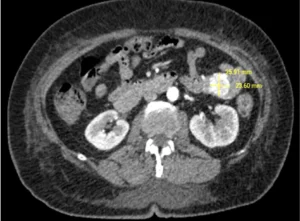

Al décimo día de hospitalización, control de hemoglobina 7.50 g/dL, hematocrito 23.20%, continúa con diagnóstico de hemorragia digestiva a determinar origen. Se realiza angiotac de aorta abdominal con reporte en el hemiabdomen izquierdo, en proyección del yeyuno, formando una lesión lobulada de 21x32x43 mm de bordes definidos, asociado a presencia de vasos ligeramente dilatados y turtuosos, adyacentes a la lesión, los cuales confluyen y se dirigen hacia la vena porta. Conclusión: malformación arteriovenosa intestinal a nivel de yeyuno.

Imagen 3. Exploración tomográfica

MAV: malformación arterio-venosa. 25,91mm x 23,60